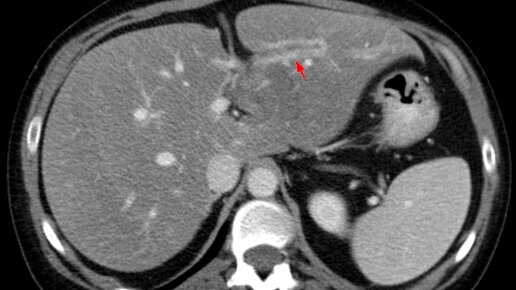

У меня камни в желчном пузыре. Можно ли избавиться от них без операции, раздробить? Желчекаменная болезнь – одно из самых распространенных заболеваний в мире: каждый 10-й мужчина и каждая 4-я женщина страдает ЖКБ. Главные причины развития данного заболевания – неправильное питание и малоподвижный образ жизни, гормональные нарушения, воспалительные заболевания желчного пузыря. Протекать ЖКБ может бессимптомно, может с клиническими проявлениями. Только врач, оценив симптомы заболевания, результаты...